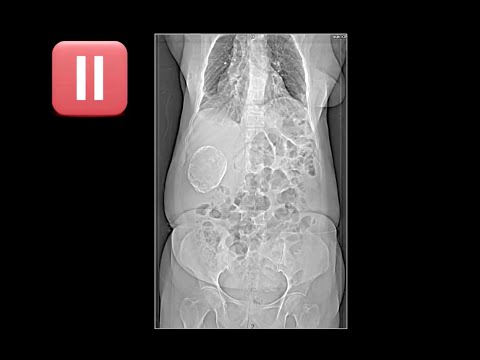

b-3-RADIOLOGY BITS (QUICK CASE 8) Get link Facebook X Pinterest Email Other Apps - May 24, 2019 Get link Facebook X Pinterest Email Other Apps Comments